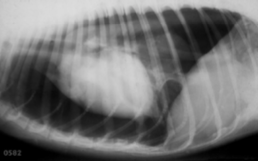

Pneumothorax